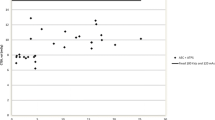

We were able to calculate the age at which CT scans were performed for all in-house scans, this ranged from 0 to 18 years, with a mean age of 6 years old. The highest number of CT scans were however seen in those children aged 0–1 year (Fig. 1). A general trend demonstrating a higher number of CT scans performed in patients who had their shunt inserted at a younger age was observed (p = 0.086), with those children undergoing insertion of shunt prior to 25 months of age being exposed to the highest number of CT scans (Fig. 2). A significant correlation between numbers of CT scans and number of shunt-years was observed (p = < 0.05), with a greater number of CT scans performed in those children who had a shunt in place for a longer period of time (Fig. 3). There appeared to be two populations in this dataset, one in which number of CTs appeared to correlate with shunt-years, and a further population in which no CT scans were performed for the first 5 years after shunting (Fig. 3).